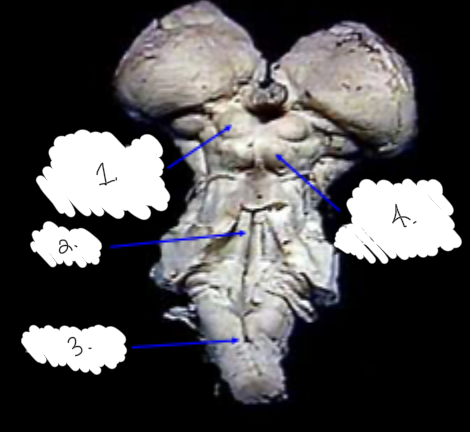

label this diagram

1: superior colliculus

2: inferior colliculus

3: pons

4: medulla